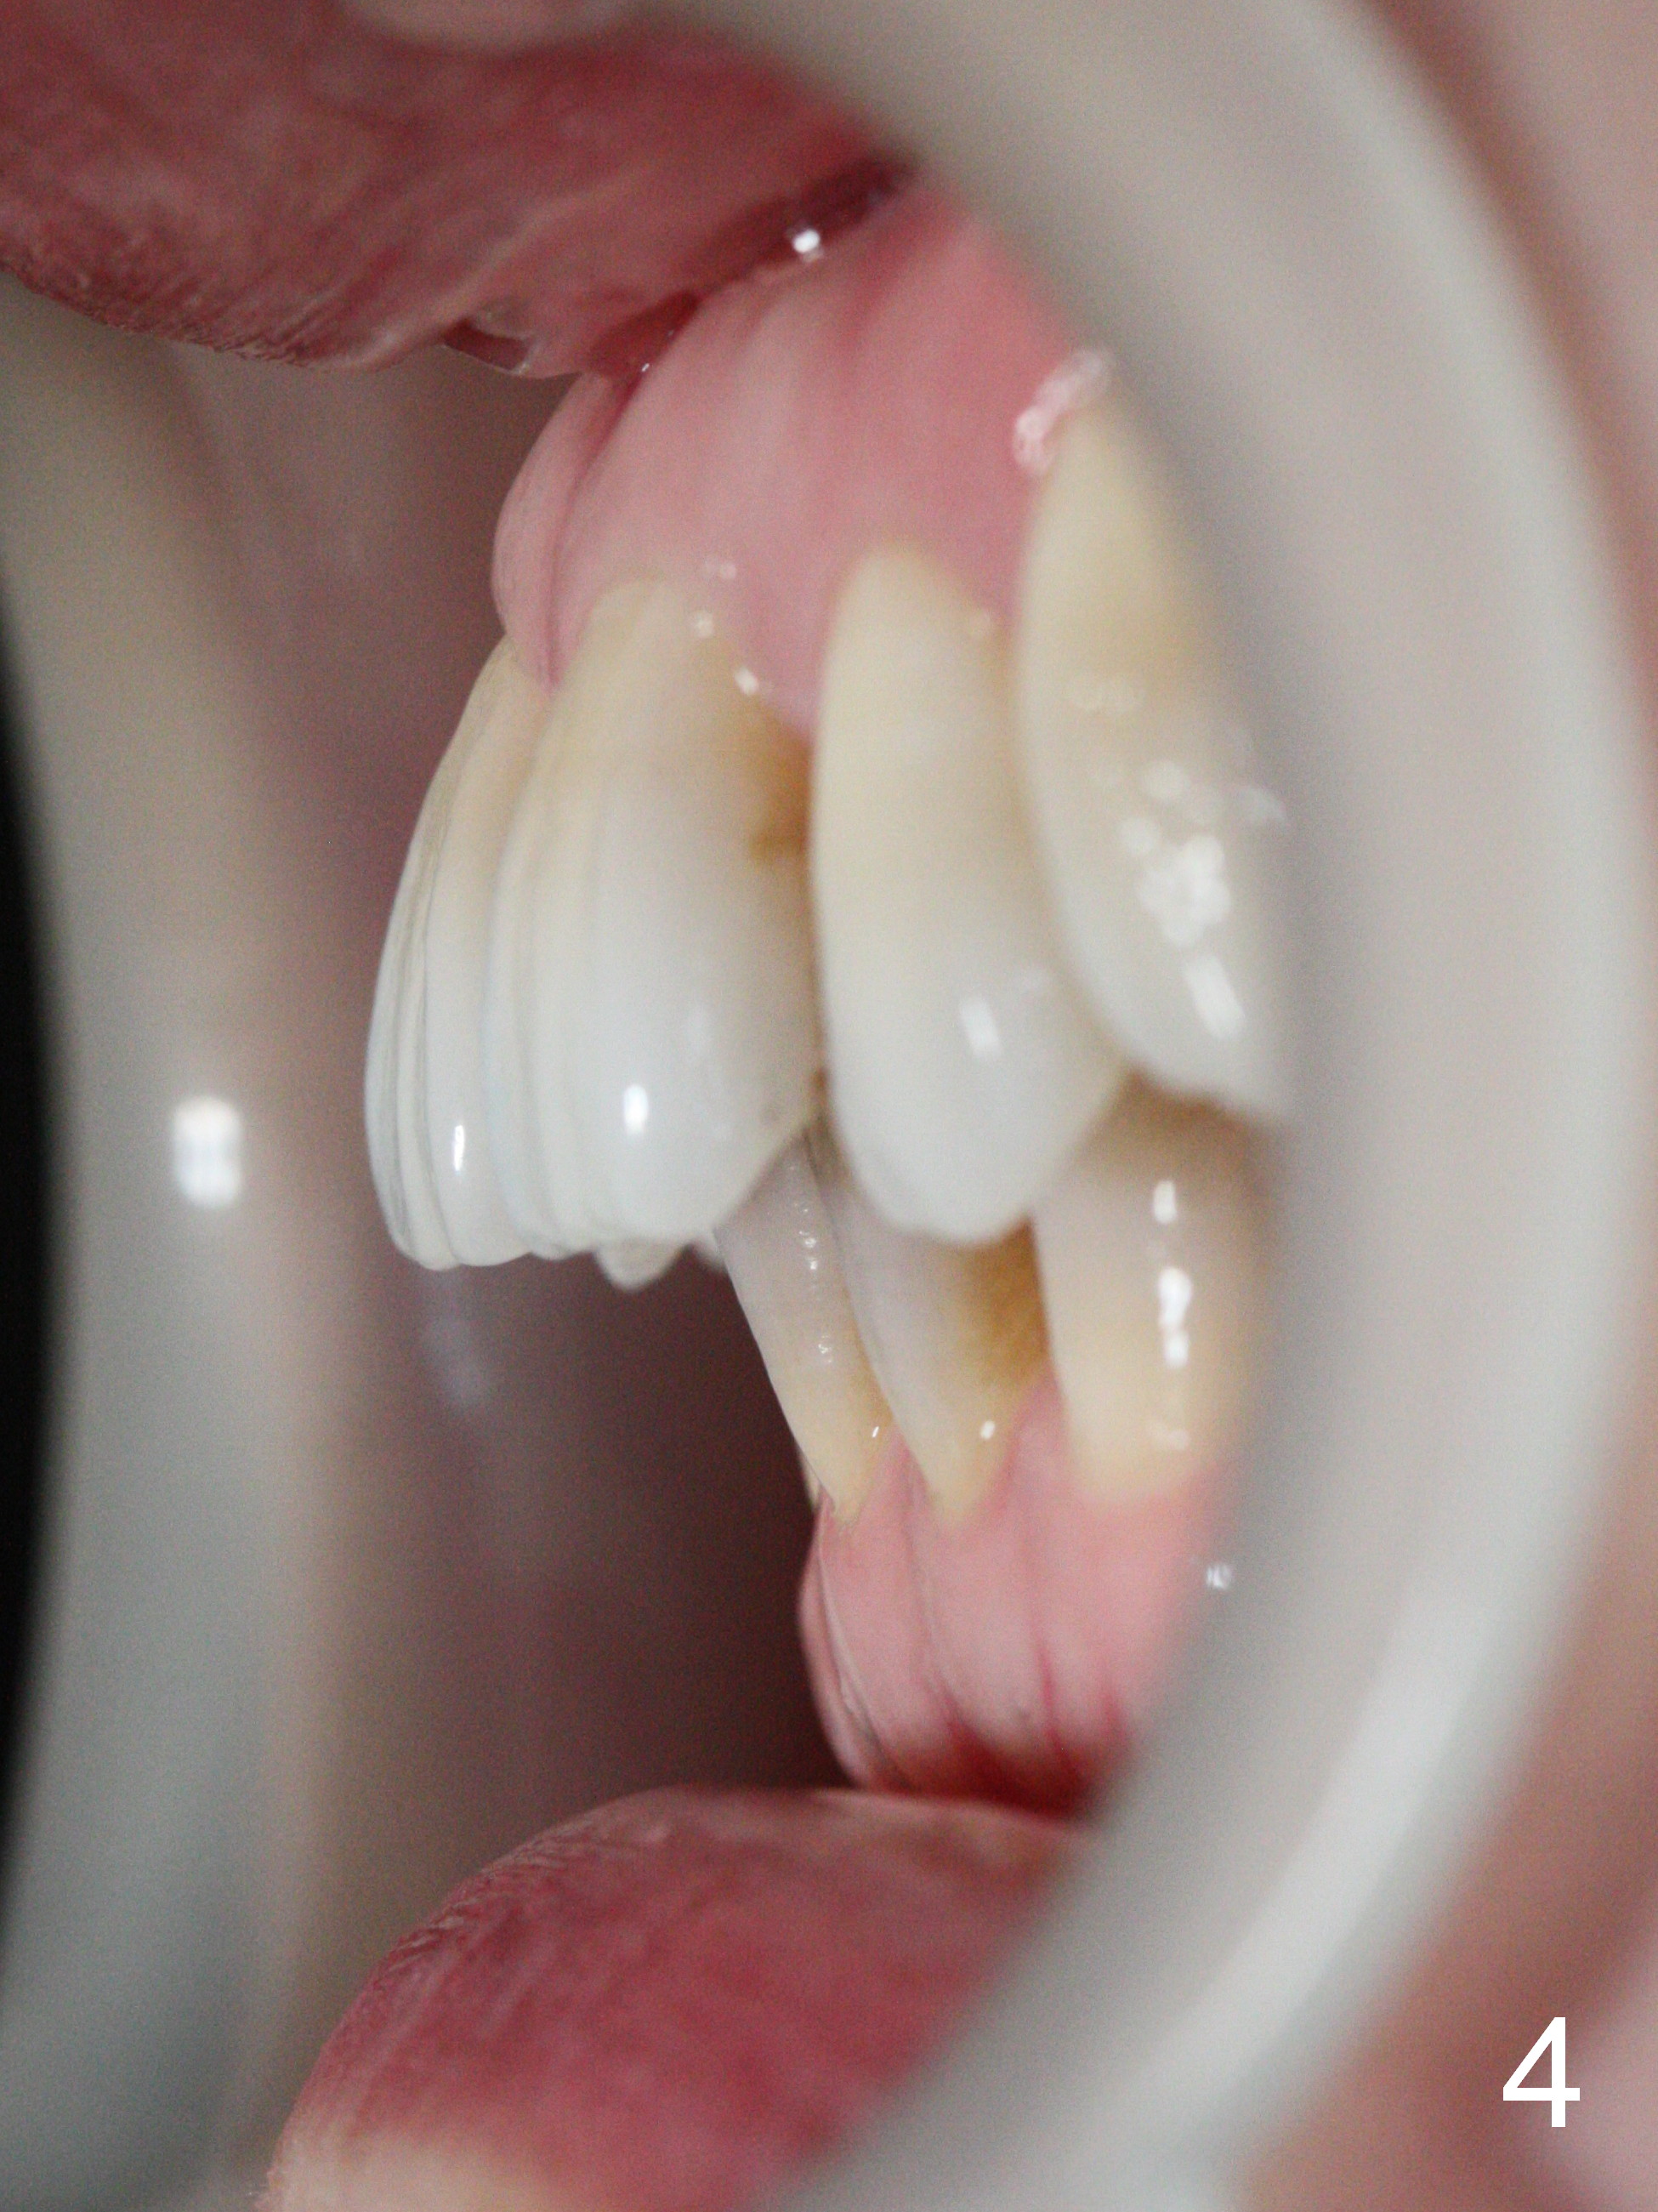

A 41-year-old woman requests orthodontic treatment because of the upper blocked out canines (Fig.6,8). Her facial and dental midlines coincide (Fig.1). Her profile is slightly convex (Fig.2,3) with increase in overjet (Fig.4). Orthodontic treatment includes extraction of U4s and placement of 2 mini-implants between U5 and 6 (Fig.5 o) when arch wires change to 18x25. Power arms (as high as possible) are placed between U2 and 3. U1-3s are retracted at the same time (en mass) because of absolute anchorage of the mini-implants. Retraction time will be reduced. Interproximal reduction (IPR) will be done especially at LR3 (macrodontia, Fig.5) if the lower arch turns out to be too large.

Fig.15-17 are taken nearly 2 months post banding. The upper 16 niti is still not fully engaged. Two weeks later, lower brackets are placed with 12 niti wire and occlusal composite (Fig.18-20). Overjet is excessive (Fig.19). Consider distalizing the upper anterior teeth when the upper arch wire changes to a rectangular one.